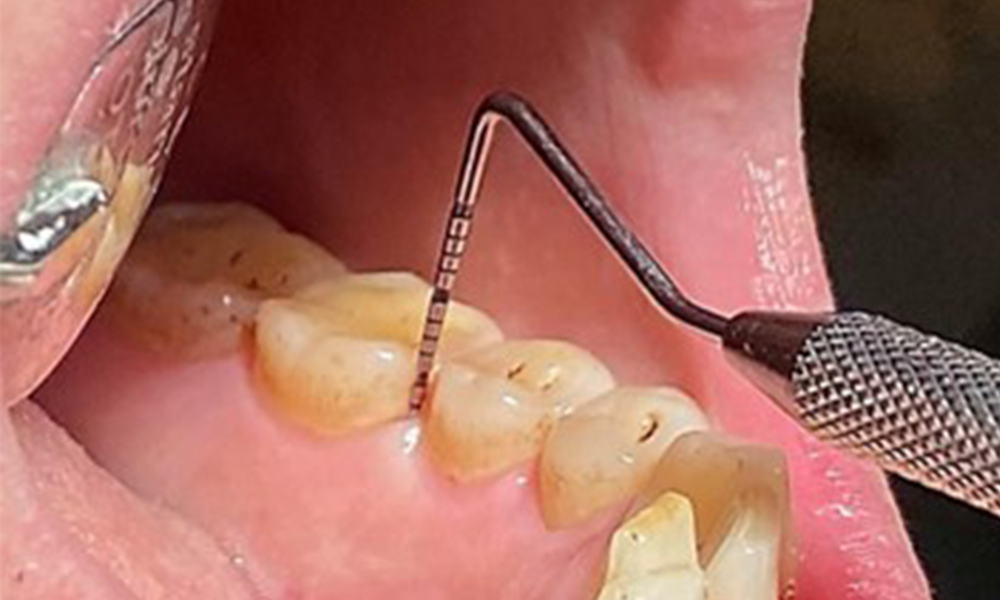

The patient is at moderate risk of current and future intraoral disease, based on their smoking status.

Due to the otherwise favourable general medical condition, the needs determined during the intraoral examination will be decisive for their treatment. It will be essential to periodically determine the probing depths. Gingival bleeding decreases in smokers, which is why the clinical diagnosis of periodontitis can only be made by probing (Fig. 7). Placing exclusive focus on the determination of bleeding indices may obscure existing periodontitis or gingivitis. (5)

Pocket probing (BOP) with depiction of tooth 36 lingual

Fig. 7 Pocket probing (BOP) with depiction of tooth 36 lingual, © Dr R. Krapf